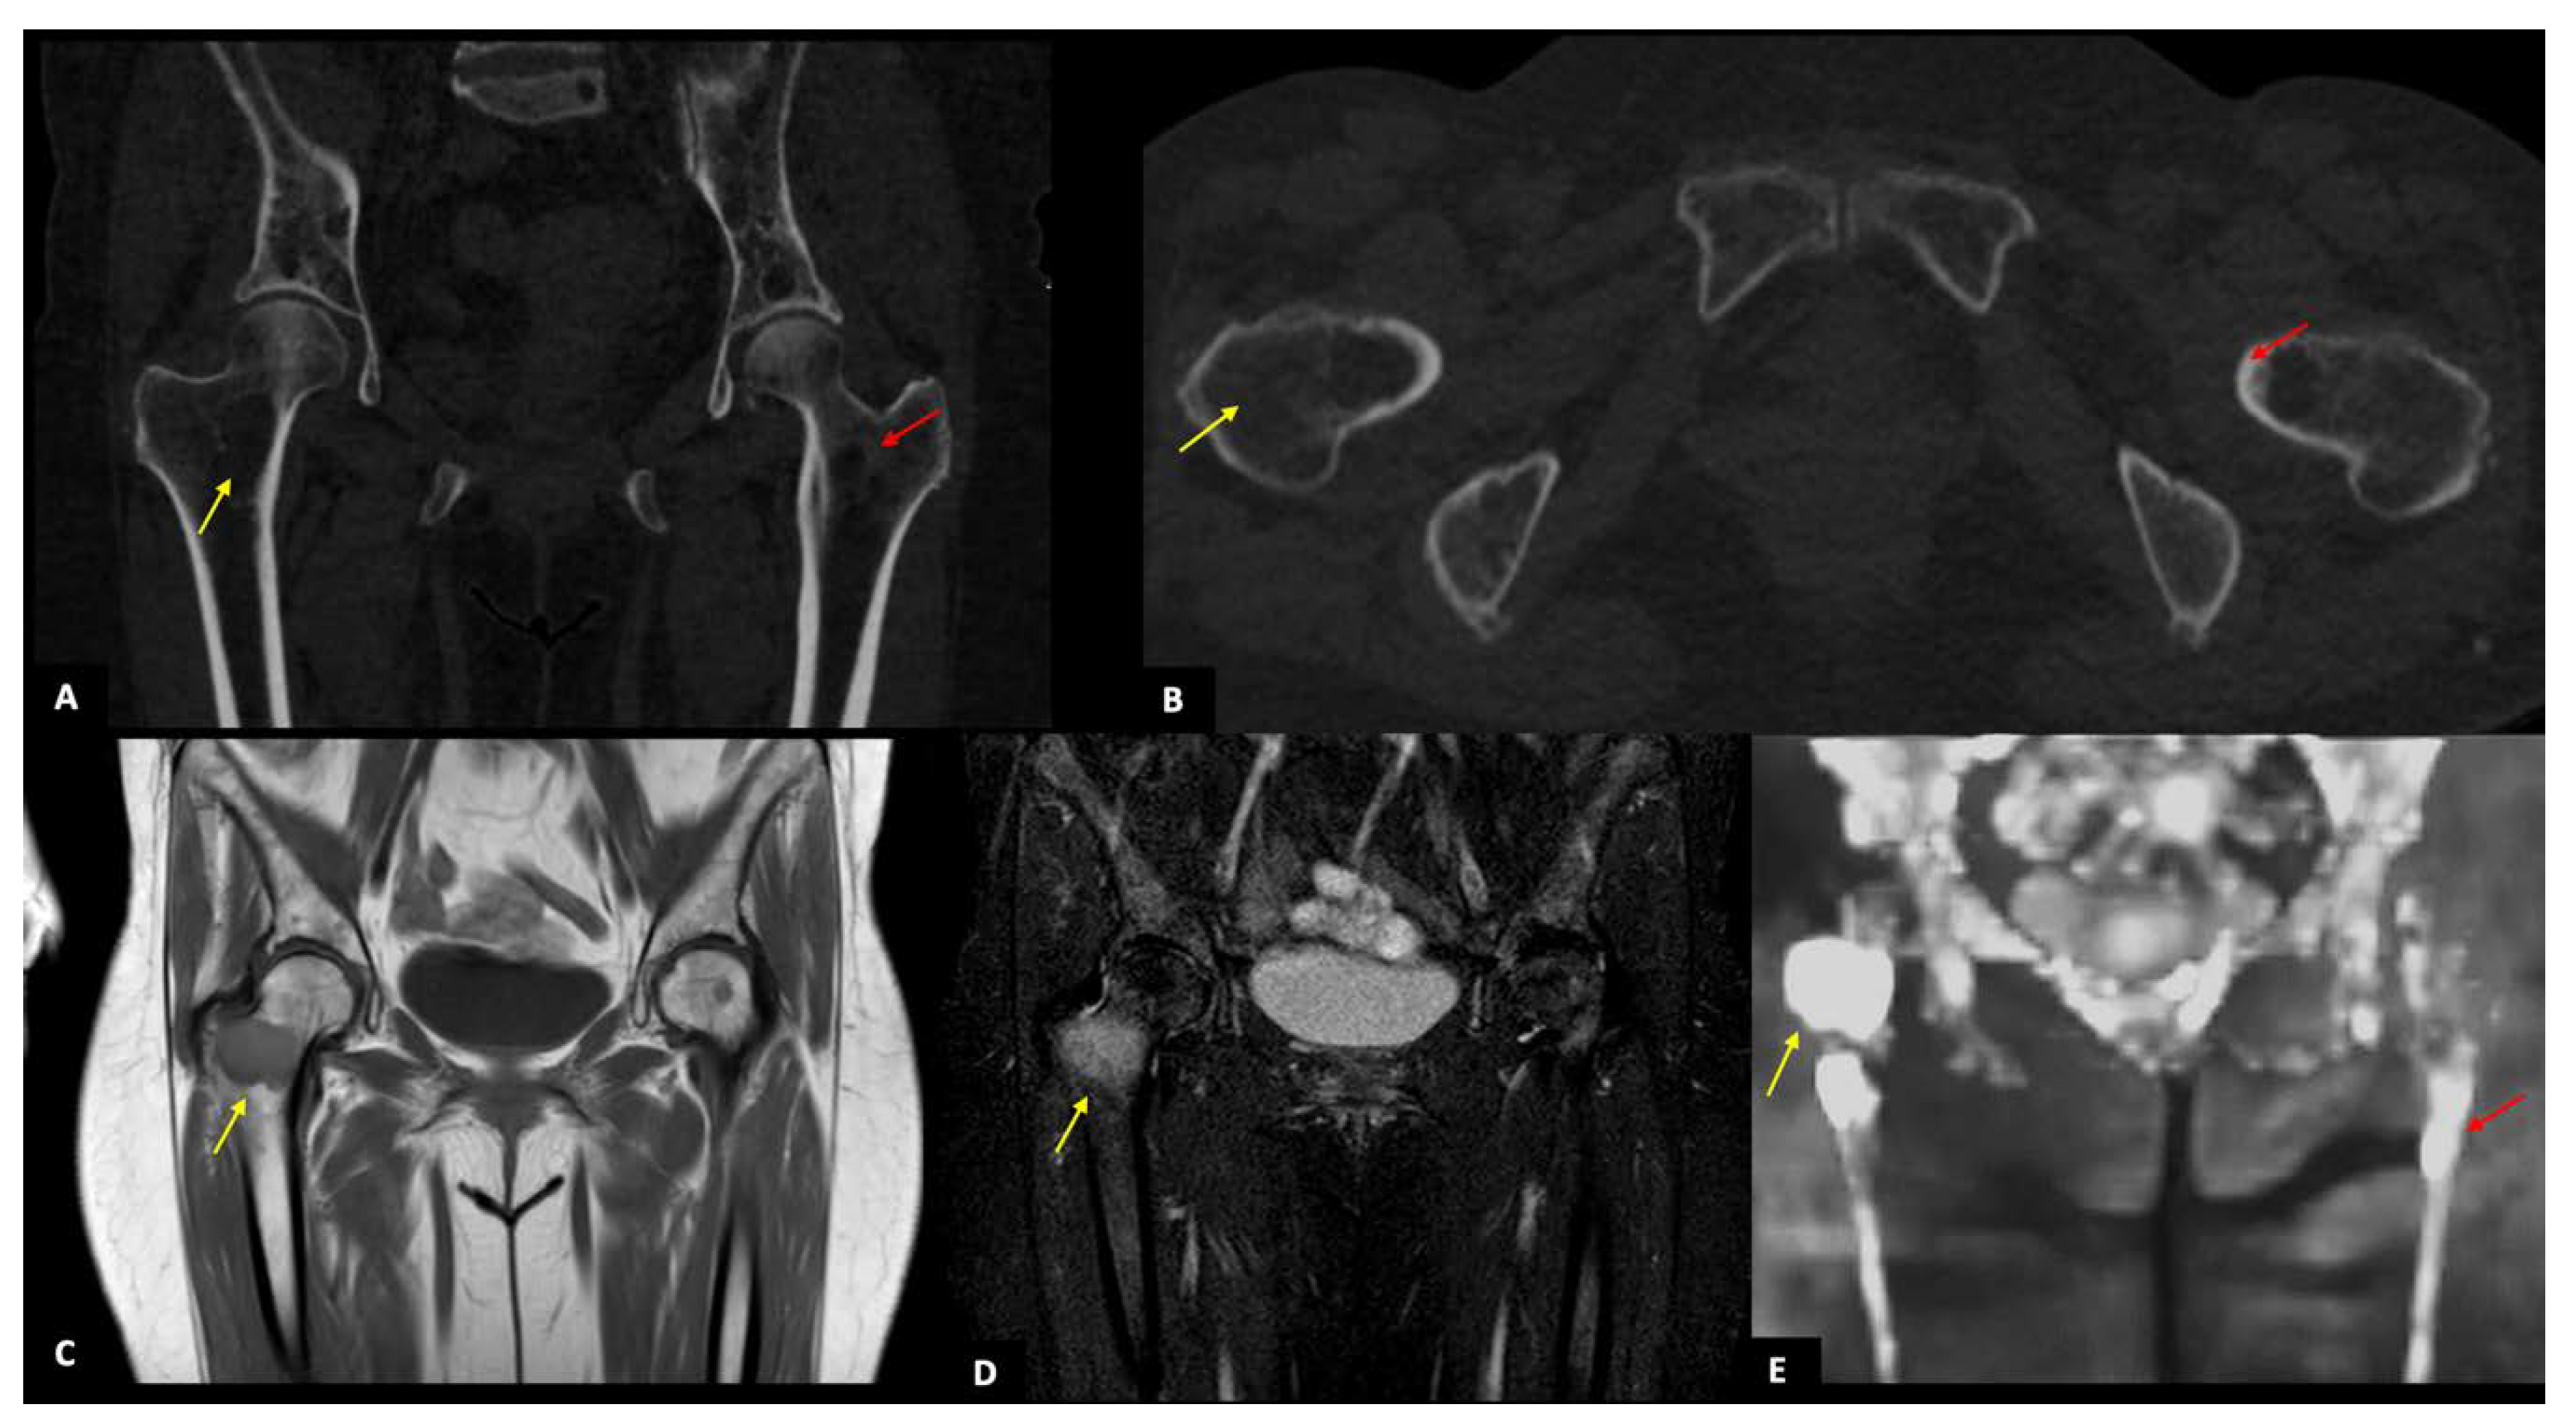

3.2. CT Findings

3.3. MRI Findings